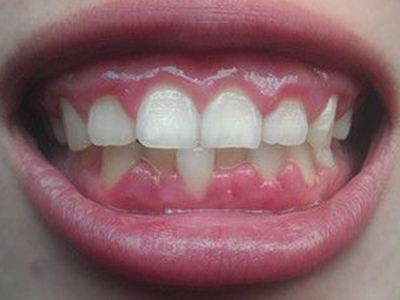

牙龈瘤多发于女性,以青年及中年人为常见,多发生于牙龈乳头部,位于唇、颊侧者较舌、腭侧者多,最常见的部位是前磨牙区。肿块较局限,呈圆形或椭圆形,有时呈分叶状,大小不一,直径由几毫米至数厘米。

肿块有的有蒂,如息肉状;有的无蒂,基底宽广,生长较慢,但在女性妊娠期间可能迅速增大。较大的肿块可以遮盖一部分牙及牙槽突,表面可见牙压痕,易被咬伤而发生溃疡,伴发感染。随着肿块的增长,牙槽骨壁逐渐被破坏,牙可能发生松动、移位。